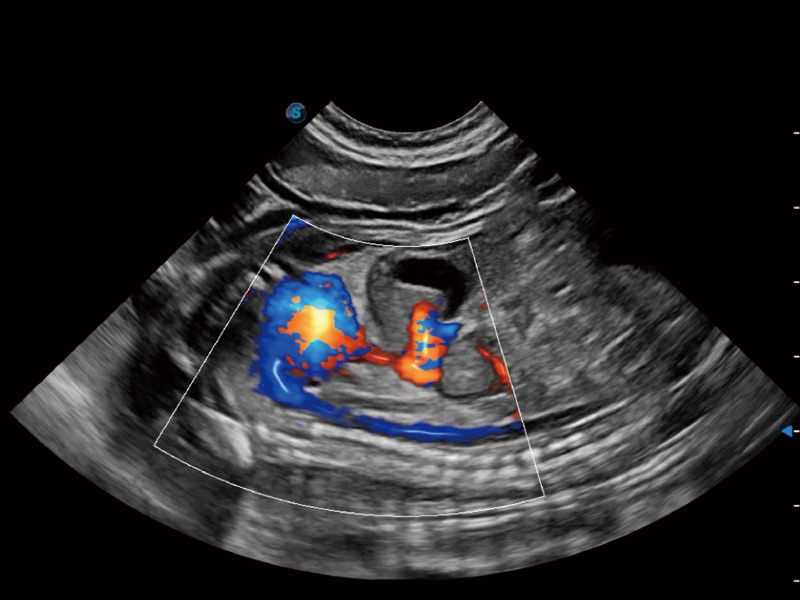

通過創(chuàng)新的 Matrix E自適應(yīng)濾波器和超長時(shí)間域算法,極大提升超低速微細(xì)血流的檢出能力,同時(shí)更精準(zhǔn)地濾除軟組織和噪聲信號,為獸用醫(yī)生提供以往無法通過常規(guī)血流獲得的疾病診斷信息。

通過色彩血流和實(shí)時(shí)寬景相結(jié)合,可觀察到完整的靜脈或動脈的血流,方便醫(yī)生檢查。實(shí)時(shí)掃查過程中,如有任何操作失誤也可以很容易地進(jìn)行回掃擦除,而不會中斷掃查。